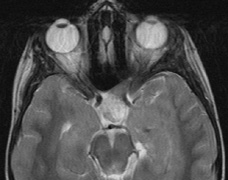

The PWS may not entirely respect the midline, possibly a reflection of transmedian innervation.212 The lesion grows proportionally with the child, often becoming darker in color. 213 The overlying skin may develop nodularity or hypertrophy in two-thirds of patients (by the fifth decade).214 Treatment with a pulsed-dye laser may significantly improve the appearance, but recurrence (i.e., redarkening) is possible.215,216 A deficit in the number of perivascular nerves in port-wine stains suggests that abnormal neural modulation of vascular flow may be involved in their pathogenesis.217 Intracranial leptomeningeal capillary vascular malformation (Figs. 21 and 22) is associated with seizures and contralateral neuromuscular weakness. Central nervous system involvement correlates highly with ipsilateral involvement of the V1 dermatome by a PWS.208,218

It has been hypothesized that the calcific changes reflect cellular anoxic injury secondary to venous stasis/poor drainage.219,220 Abnormal autonomic innervation has also been reported in association with the malformed cortical vessels—innervation only by noradrenergic fibers.221 Studies suggest that the normal increase in brain-blood flow to accommodate increased metabolic demand during seizure activity is blunted in affected brain regions of SWS.222 Thus, seizures in the setting of impaired perfusion may be exacerbating brain injury. Periods of contralateral weakness (days to weeks) can follow a prolonged seizure episode.206,223 When seizures begin early in life, the risk of developmental delay is much higher. In a review of 171 patients with a facial PWS and associated intracranial vascular malformation, 80% were found to have a seizure disorder. Of those, 75% with seizures had an onset during the first year of life, rising to 95% before age 5 years. Nearly all patients had a PWS that included (or was limited to) the V1 distribution. Developmental delay was strongly associated with seizures (71% of children with seizures as compared to 6% without seizures).224 Glaucoma affects 50% to 70% of SWS patients224,225 and it is a therapeutic challenge. From the time of diagnosis, the intraocular pressure, the optic discs, and the corneal diameters need to be measured intermittently, even if an occasional examination under anesthetic is required. The development of glaucoma appears to follow a bimodal age distribution: early-onset/congenital-type and later-onset. The glaucomatous eye is nearly always on the same side as the PWS.224 The highest risk for glaucoma appears to be when the PWS involves both the upper and lower lid: 72% vs. 21% for VI-only (upper eyelid) involvement in one study.224 The bimodal age distribution of glaucoma suggests that more than one mechanism is involved. Angle abnormalities (“trabeculodysgenesis” with or without flat anterior iris insertion) have been reported in association with the early-onset/congential type.225 Other proposed mechanisms include uveal capillary dilation226 and elevated episcleral venous pressure. Reports of blood in Schlemm's canal on gonioscopy support the idea of increased episcleral venous pressure pathomechanics.227,228 Glaucoma in SWS often responds poorly to medical therapy alone. The “trabeculodysgenesis” of early onset Sturge-Webber glaucoma is reported to be similar in gonioscopic appearance to primary congenital glaucoma.229 On this basis, goniotomy was suggested as a treatment of choice in early-onset SWS glaucoma. One group looked at the success of goniotomy, trabeculotomy, trabeculectomy, laser trabeculoplasty and medication in the management of SWS-associated glaucoma.230 In the early onset subgroup receiving goniotomy, median stable interval of intraocular pressure reduction after one procedure was 8 months; with multiple goniotomies and the addition of medical treatment, the median stable interval was extended to 9 years. Other investigators have found that goniotomy alone may be insufficient, requiring filtering surgery at some point. However, trabeculectomy carries a significant risk of choroidal expansion in association with hypotony. Theoretically, the risk may be higher when there is increased choroidal vascularity in association with the facial PWS—a “tomato ketchup” fundus.231 Often, there is associated increased tortuosity of the retinal vessels as well. Placement of a prophylactic posterior sclerotomy prior to filtering surgery to prevent choroidal expansion is controversial.232 Cryo- or thermocoagulation of the ciliary body in combination with medical therapy may be an alternative to surgery.233 KLIPPEL TRENAUNAY—WEBER SYNDROME Klippel-Trenaunay syndrome consists of combined capillary, lymphatic, and venous malformations, in association with varicosities and limb enlargement (Fig. 23). In the majority of cases, the lower limb is affected.234,235